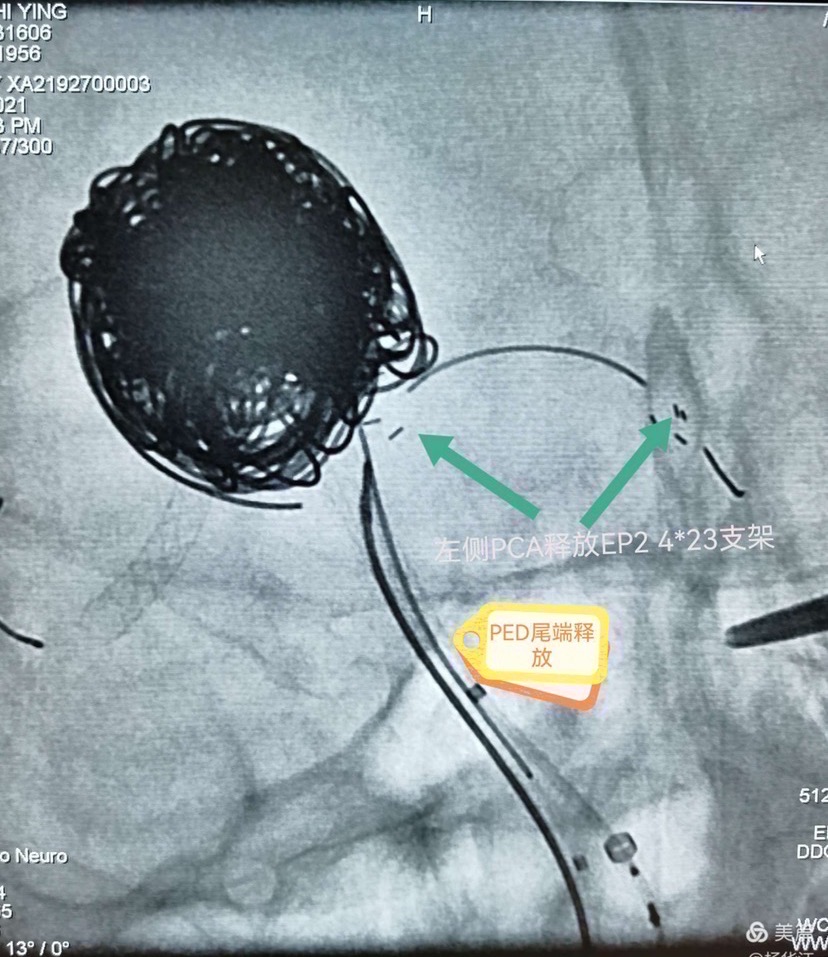

然后填圈至动脉瘤中、上部致密填塞,下部近分支处疏松填塞,同时释放左侧EP2支架,尾端紧贴pipeline侧方呈T形放置。最后稍推拉完全pipeline至基底动脉中下段。(这是本次手术有瑕疵的地方,尾端覆盖基底动脉稍长了一些,与我们测量计算误差有关)

术后即刻造影显示瘤体中上部已完全不显影,仅下部可见造影剂,基底动脉各分支显影良好。